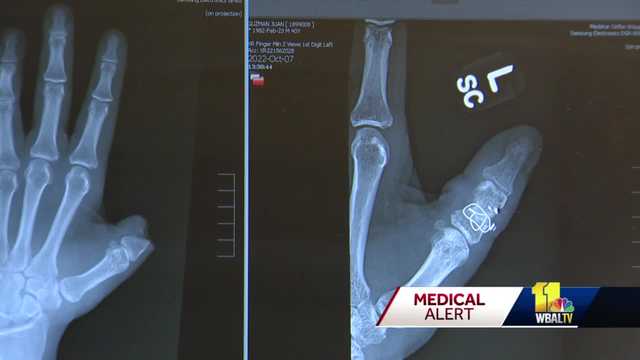

Man thankful to surgeons for his dexterity after losing thumb in dog bite wbaltv.com/article/baltim…